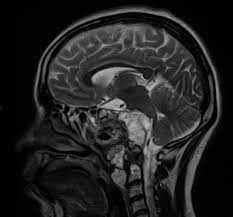

Los tumores selares y supraselares son neoplasias que se desarrollan en la región de la silla turca, una estructura ósea que alberga la glándula hipófisis en la base del cráneo. la presencia de tumores en estas áreas puede afectar la función normal de la hipófisis, generar síntomas relacionados con la compresión de estructuras circundantes y, en algunos casos, provocar disfunciones hormonales.

La hipófisis, también conocida como glándula pituitaria, ocupa una posición anatómica destacada en la base del cerebro, alojada en una depresión ósea específica denominada silla turca, parte integral del hueso esfenoides. Esta ubicación estratégica asegura la protección y alineación precisa de la glándula en el contexto craneal.

El tallo hipofisario, una estructura anatómica clave, emerge de la hipófisis y establece una conexión vital con el hipotálamo en el cerebro. Este tallo no solo transporta las hormonas producidas por el hipotálamo hacia la hipófisis, sino que también atraviesa una abertura específica en la duramadre conocida como diafragma de la silla o selar. Este orificio en la membrana contribuye a la correcta disposición y funcionamiento de la conexión entre la hipófisis y el hipotálamo.

En el entorno anatómico cercano, específicamente por delante del tallo hipofisario y a una distancia de 5-10 mm por encima de la silla turca, se encuentra el quiasma óptico. Este componente es esencial en el sistema visual, ya que representa el punto en el cual las fibras de los nervios ópticos parcialmente se entrecruzan. Este cruce permite la interconexión entre las mitades contralaterales del campo visual, contribuyendo así a la percepción visual integrada.